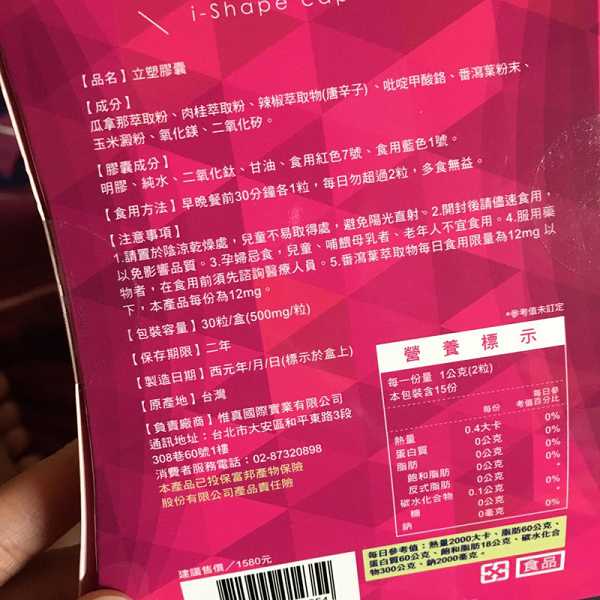

Supercut塑魔纖立塑膠囊的成分有:瓜拿那萃取粉、肉桂萃取粉、辣椒萃取物(唐辛子)、吡啶甲酸鉻、番瀉葉粉末、玉米澱粉、氧化鎂、二氧化矽。

之前上過相關課程,成分表是依照每項成分的多寡來排列順序,排在最前面的就是產品的主要成分!

那我就跟大家分享瓜拿那萃取粉、肉桂萃取粉和辣椒萃取物吧

瓜拿那萃取和辣椒萃取是可以幫助纖體瘦身常見的營養素!

1.「瓜拿那」是原產於亞馬遜流域的一種藤蔓植物,富含酵素可以幫助排便順暢,並且能抑制脂肪分解酵素,此外也有降低食慾的效果喔~~萃取物中含有天然咖啡因,可以提高新陳代謝率以及排出多餘水分!

2.「辣椒萃取物」則是可以幫助體內脂肪燃燒、增加卡路里的消耗,達到防止脂肪積聚的效果

3.「肉桂萃取物」看到肉桂,就想到麥當勞的蘋果派或是手掌麵包,雖然很多人很害怕那味道,但艾哥愛死肉桂了!!!!肉桂在古代被視為是最有價值的東方香料之ㄧ,中世紀時,肉桂的聲望僅次於昂貴的黑胡椒,除了香料和薰香價值, 傳統上肉也被用來治療消化不良、脹氣、關節疼痛、出血和經痛,研究也指出肉桂可以促進新陳代謝喔

食用方式:早晚餐前30分鐘各1粒,每日不超過2粒。(多食無益)

番瀉葉萃取物每日食用限量為12mg以下,

番瀉葉萃取物每日食用限量為12mg以下,

鉻與脂肪代謝有關,有助於控制血液中的膽固醇,並有降低血壓的作用,可以預防高血壓,對降低體重也有不錯的效果。

鉻與脂肪代謝有關,有助於控制血液中的膽固醇,並有降低血壓的作用,可以預防高血壓,對降低體重也有不錯的效果。